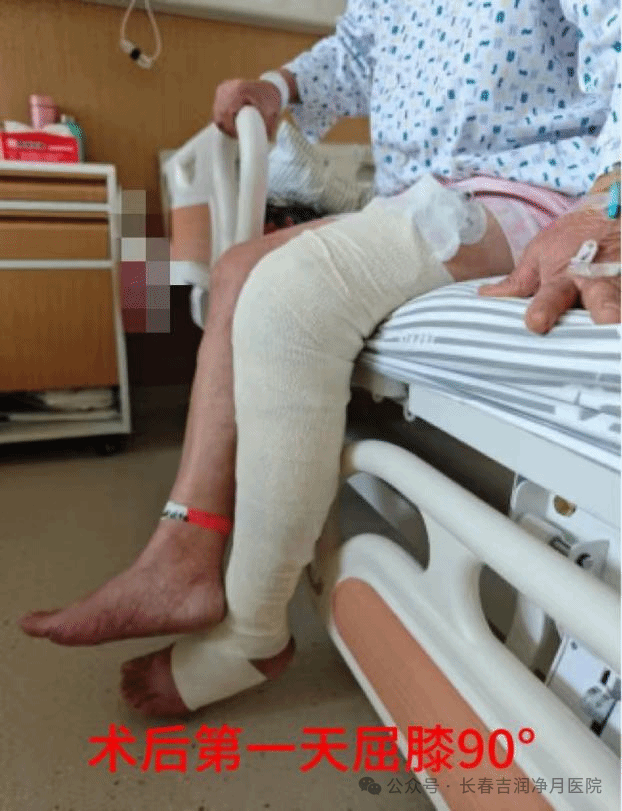

“不仅技术好,医生护士还天天来问疼不疼、想吃啥,比家人还细心”,胥奶奶拉着护士的手感慨道。在院期间,护理团队在牛越护士长的带领下,依据ERAS快速康复及全程无痛理念,为患者制定了科学系统个性化的康复计划,动态监测患者的膝关节功能恢复情况、疼痛程度及各项生命体征,围手术期NRS评分<4分。由责任护士一对一指导股四头肌收缩训练,并耐心讲解康复原理,缓解其紧张情绪。患者术后当天膝关节屈曲活动度达 90°,术后第1天即可辅助行走。